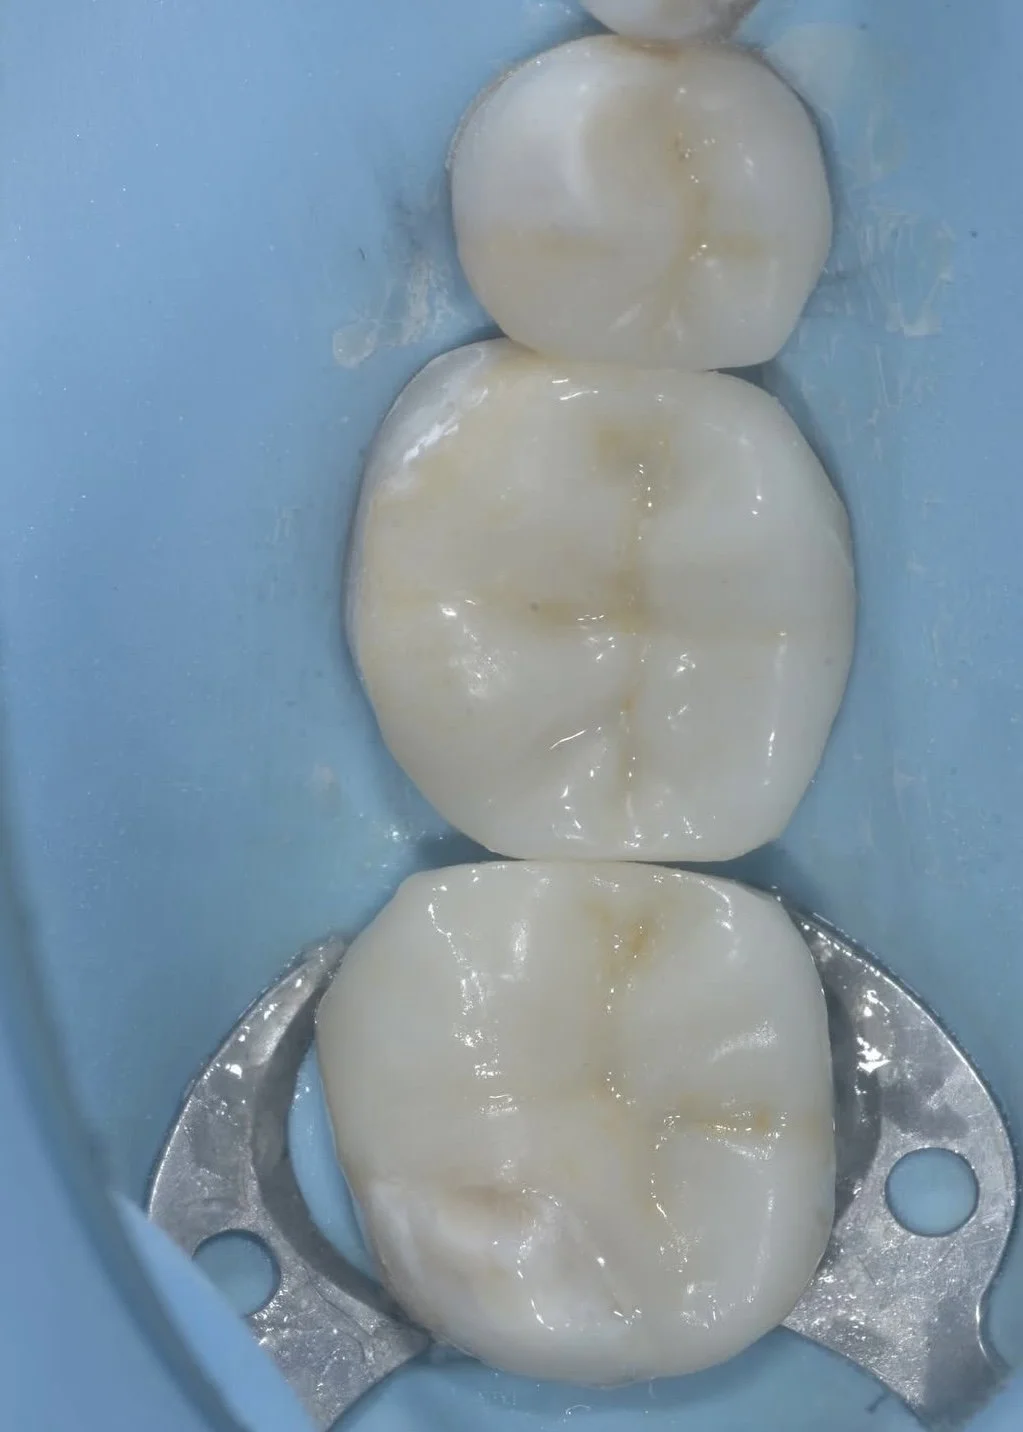

These photos of a traditional crown replacement and a biobase with a conserved biorim showing the difference in tooth structure between the preparations. Cases by Dr. Davey Alleman, DMD.

When treating large failing restorations, full coverage crows are no longer necessary. The advanced adhesive protocols of biomimetic dentistry allow critical tooth structure in the biorim to be conserved. Case by Dr. Davey Alleman, DMD.

This case by Dr. Davey Alleman, DMD shows how the Six Lessons Approach protocols eliminate the need for full coverage crowns with predictable dentin bonding protocols.